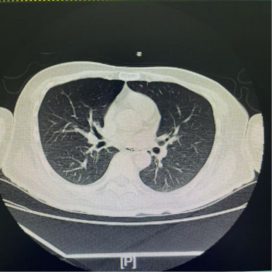

主管医生多次尝试堵管(封闭气切套管口,观察能否自主呼吸),但每次都以失败告终。原因很简单:只要一堵管,张大爷就憋得满脸通红,血氧饱和度急剧下降。胸部CT显示,他的右下肺呈现不张状态,大量的痰液像“淤泥”一样堵塞了深部的支气管。

术后复查胸部CT显示:原本不张的右下肺已基本复张。医生再次尝试堵管,张大爷呼吸平稳,没有丝毫憋闷感。